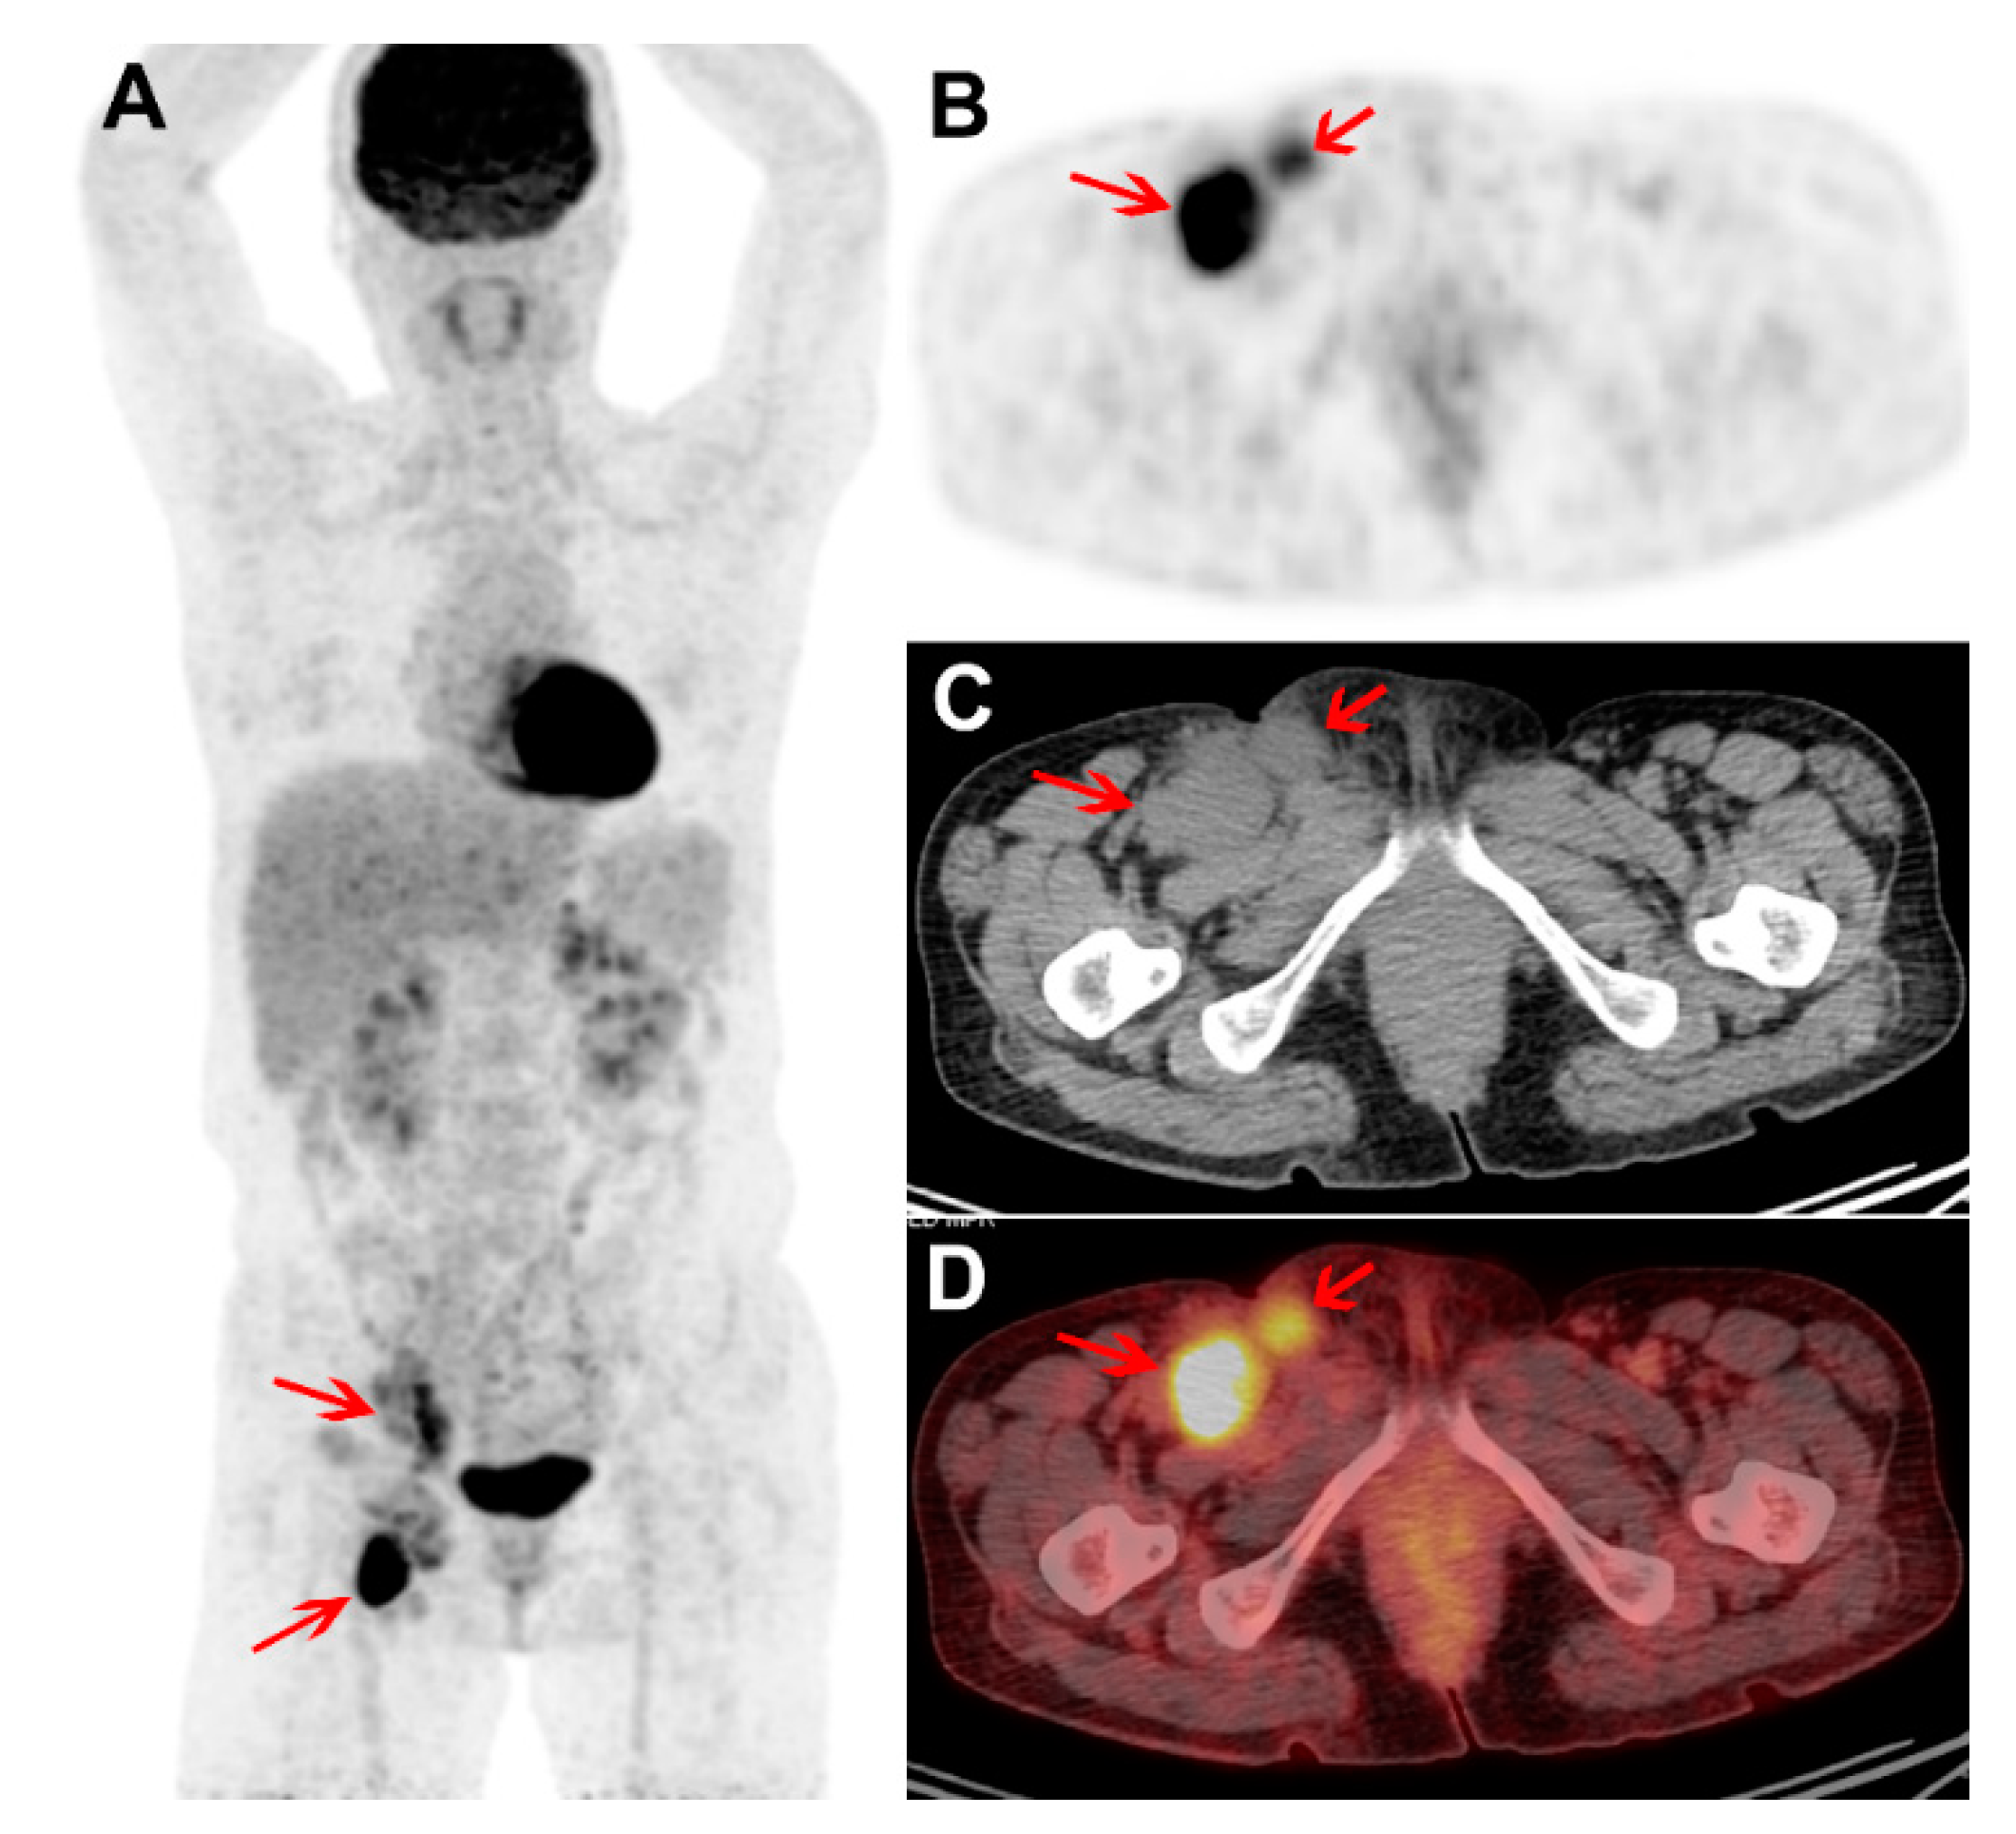

3.2. Visual Assessment of FDG PET/CT

3.3. Quantitative Assessment of FDG PET/CT